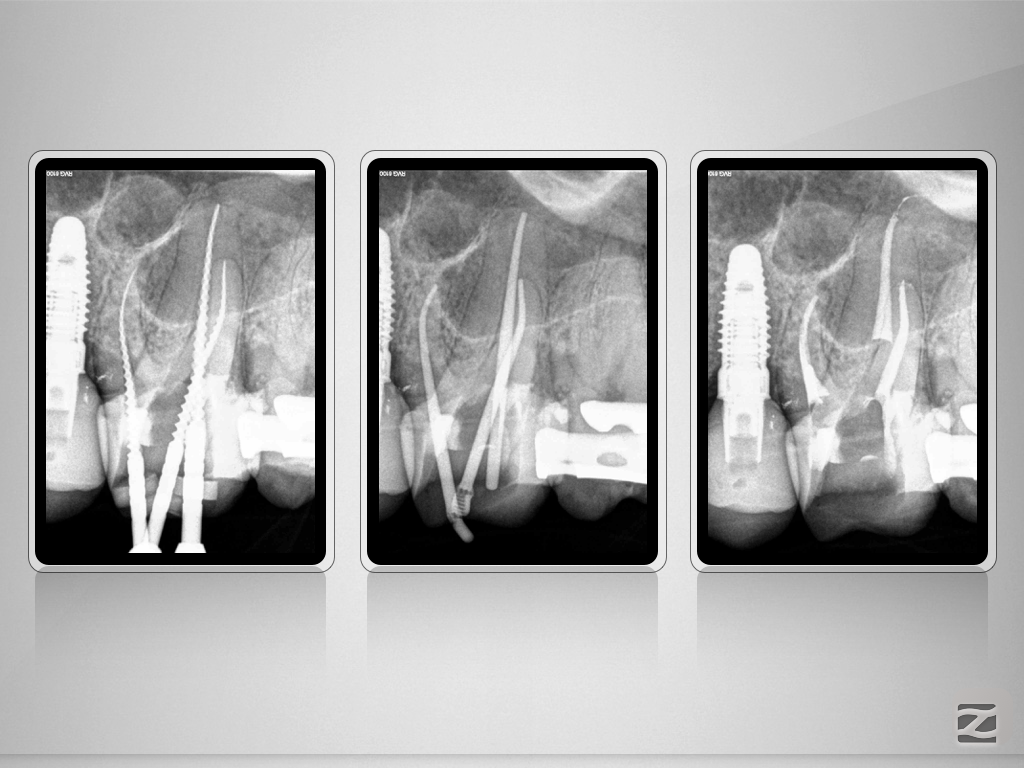

26D.005

Das Mikroskop-Bias